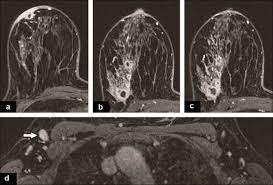

What Does Inflammatory Breast Cancer Look Like On Mri - Breast Cancer Gynecology And Obstetrics Msd Manual Professional Edition / Inflammatory breast cancer pictures show a red and/or swollen breast that appears inflamed.. You may notice dimpling or pitting, and the skin on your breast. Cancer begins when uncontrollably change and grow, forming a sheet of cells called a tumour. It blocks the lymph vessels in the skin of your breast. Inflammatory breast cancer inflammatory breast cancer is a rare type of breast cancer that develops rapidly, making the affected breast red, swollen and tender. Symptoms of inflammatory breast cancer include swelling (edema) and redness (erythema) that affect a third or more of the breast.

When the cancer grows into the rest of the body through the blood vessels and lymph vessels, breast cancer spreads. Inflammatory breast cancer occurs when cancer cells block the lymphatic vessels in skin covering the breast, causing the characteristic red, swollen appearance of the breast. Inflammatory breast cancer inflammatory breast cancer is a rare type of breast cancer that develops rapidly, making the affected breast red, swollen and tender. A breast mri usually is performed after you have a. The usual cause of inflammatory breast symptoms is breast mastitis or duct ectasia.

The features of a malignant breast condition on mri scan are often to do with the outer irregular borders of a lesion. Inflammatory breast cancer affects breast tissue and can appear unusually dimpled or thick. Absence of lump or breast mass in a patient suffering from an inflammatory skin condition of the breast, suggests the presence of skin or subcutaneous inflammatory condition caused by either infection or inflammatory breast cancer. The skin looks like the skin of an orange, and may be discolored with painful and itchy breast. The breast is enlarged (often of relatively short onset), indurated, erythematous, warm, and may be tender and painful. But not every woman who has been diagnosed with breast cancer needs a breast mri. What does breast cancer look like on a mammogram? A lump in the breast. Breast mri is sometimes used in women who already have been diagnosed with breast cancer, to help measure the size of the cancer, look for other tumors in the breast, and to check for tumors in the opposite breast. Most cases are invasive ductal carcinomas, which develop in the cells lining the milk ducts and spread throughout the breast. The breast can also be painful in inflammatory breast cancer, but this is not always the case. Evaluating the impact of preoperative breast magnetic resonance imaging on the surgical management of newly diagnosed breast cancers. When the cancer grows into the rest of the body through the blood vessels and lymph vessels, breast cancer spreads.

Inflammatory breast cancer is an an aggressive and fast growing breast cancer in which cancer cells infiltrate the skin and lymph vessels of the breast. They're often easy to move around (mobile) and may be tender. Ibc symptoms are caused by cancer cells blocking lymph vessels in the skin causing the breast to look inflamed. symptoms include breast swelling, purple or red color of the skin, and dimpling or thickening of the skin of the breast so that it may look and feel like an orange peel. Unlike traditional forms of breast cancer, inflammatory breast cancers do not develop unusual lumps within the affected breast. The skin is thickened and edematous, classically with a peau d'orange appearance. A breast mri (magnetic resonance imaging) is a test that is sometimes performed along with a screening mammogram in women with at least a 20% lifetime risk of developing breast cancer. What does breast cancer look like on a mammogram? Mri of breast can help breast cancer diagnosis. Inflammatory breast cancer inflammatory breast cancer is a rare type of breast cancer that develops rapidly, making the affected breast red, swollen and tender. A rash isn't the only visual symptom of inflammatory breast cancer. Inflammatory breast cancer (ibc) is rare, making up about 2 to 4 percent of breast cancer cases. Inflammatory breast cancer pictures and symptoms The skin looks like the skin of an orange, and may be discolored with painful and itchy breast.

Inflammatory breast cancer occurs when cancer cells block the lymphatic vessels in skin covering the breast, causing the characteristic red, swollen appearance of the breast. A rash isn't the only visual symptom of inflammatory breast cancer. Inflammatory breast cancer inflammatory breast cancer is a rare type of breast cancer that develops rapidly, making the affected breast red, swollen and tender. J natl compr canc netw. A lump in the breast.